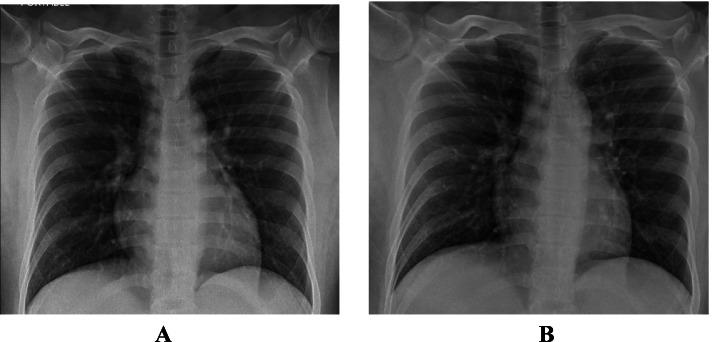

This is a retrospective case series study. We have included seven pregnant women admitted with early COVID-19 infection to a tertiary care hospital, Latifa Maternity Hospital in Dubai, United Arab Emirates between 12 February and 04 March 2021 and who consented to receive COVID-19 convalescent plasma as part of their treatment plan. Main outcomes measured were clinical and radiological features, laboratory tests, WHO clinical progression scale pre and post treatment, and maternal, fetal outcomes. COVID-19 clinical severity was classified according to the NIH guidelines for criteria of SARS-CoV-2. For the radiological features, a modified chest X-ray scoring system was used where each lung was divided into 6 zones (3 on each side upper, middle, and lower). Opacities were classified into reticular, ground glass, patchy and dense consolidations patterns.

这是一项回顾性病例系列研究。我们纳入了 2021 年 2 月 12 日至 3 月 4 日期间在阿拉伯联合酋长国迪拜拉蒂法妇产医院因早期 COVID-19 感染住院且同意接受 COVID-19 恢复期血浆治疗的 7 名孕妇。主要观察指标为临床和影像学特征、实验室检查、治疗前后世界卫生组织临床进展量表(WHO 临床进展量表)以及母婴结局。根据 NIH 指南,COVID-19 临床严重程度分为 SARS-CoV-2 标准。对于影像学特征,使用改良的胸部 X 线评分系统,每个肺分为 6 个区(每侧上、中、下各 3 个区)。将不透明性分为网状、磨玻璃、斑片状和致密性实变。